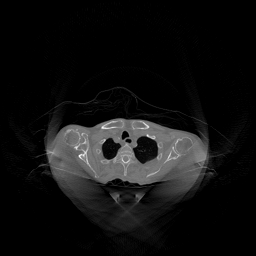

III-D Real Clinical Data Experiment

The experimental results on clinical head data are shown in Fig. 4. The reference images were reconstructed using the fast iterative shrinkage-thresholding algorithm (FISTA) with total variation regularization from non-truncated projection data. In the WCE reconstructions (Fig. 4(b)), severe truncation prevents accurate recovery of anatomical structures outside the FOV. Despite being trained solely on simulated data with a domain gap, all deep learning models can restore a substantial portion of the missing anatomy. Among them, the diffusion-based methods recover soft-tissue boundaries more faithfully than the conventional deep learning approach FBPConvNet, highlighting their stronger image generation capability. However, cDDPM reconstructions exhibit more noticeable noise than those from other methods, consistent with the simulated data results. The patchDiffusion model introduces artifacts within the FOV, likely due to its patch-wise processing strategy. While I2SB shares the same limitations as other diffusion models in perfectly restoring soft-tissue detail, it produces fewer residual noise patterns and fewer artifacts within the FOV boundaries. Overall, Fig. 4 demonstrates the strong efficacy of I2SB in reconstructing real CBCT data.

| Methods | RMSE | PSNR | SSIM |

|---|---|---|---|

| FBP | 425.3 | 19.68 | 0.4372 |

| WCE | 382.2 | 21.16 | 0.6642 |

| Pix2pixGAN | 279.8 | 23.41 | 0.5702 |

| FBPConvNet | 260.0 | 24.19 | 0.6181 |

| cDDPM | 190.2 | 26.94 | 0.6482 |

| patchDiffusion | 231.8 | 25.25 | 0.6839 |

| diffusionGAN | 162.1 | 28.19 | 0.6798 |

| I2SB (proposed) | 152.0 | 28.72 | 0.7260 |